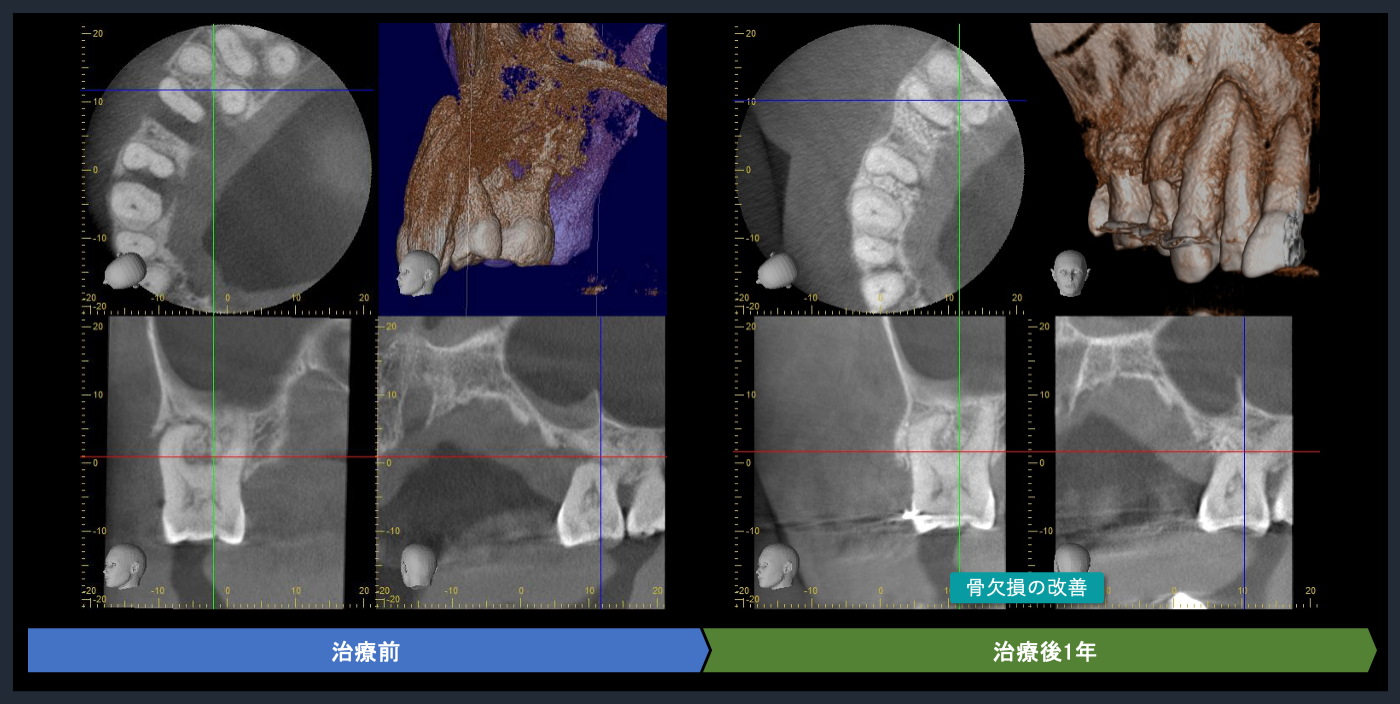

| 概要 | 歯周病が進行しており、右上臼歯部に重度の骨吸収像が認められます。失われた骨を再生し、歯の生存率を高めることを目的に、再生療法を試みました。良好な結果を得ることができました。問題なく使っていただいております。 再生療法を行う利点としては、ポケットが浅くなるので、患者様ご自身でのブラッシングで管理し、コントロールすることが可能になります。もちろん定期的なメインテナンスは必要不可欠です。 |

CTでの術前診査1

歯周基本治療後の再評価

Post-treatment evaluation

Post-treatment evaluation

CTでの術前診査2